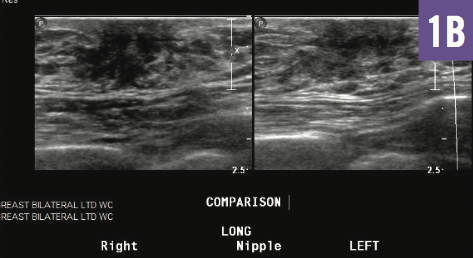

Interactive Quiz: Galactorrhea as the Initial Presentation of a Hepatic Condition